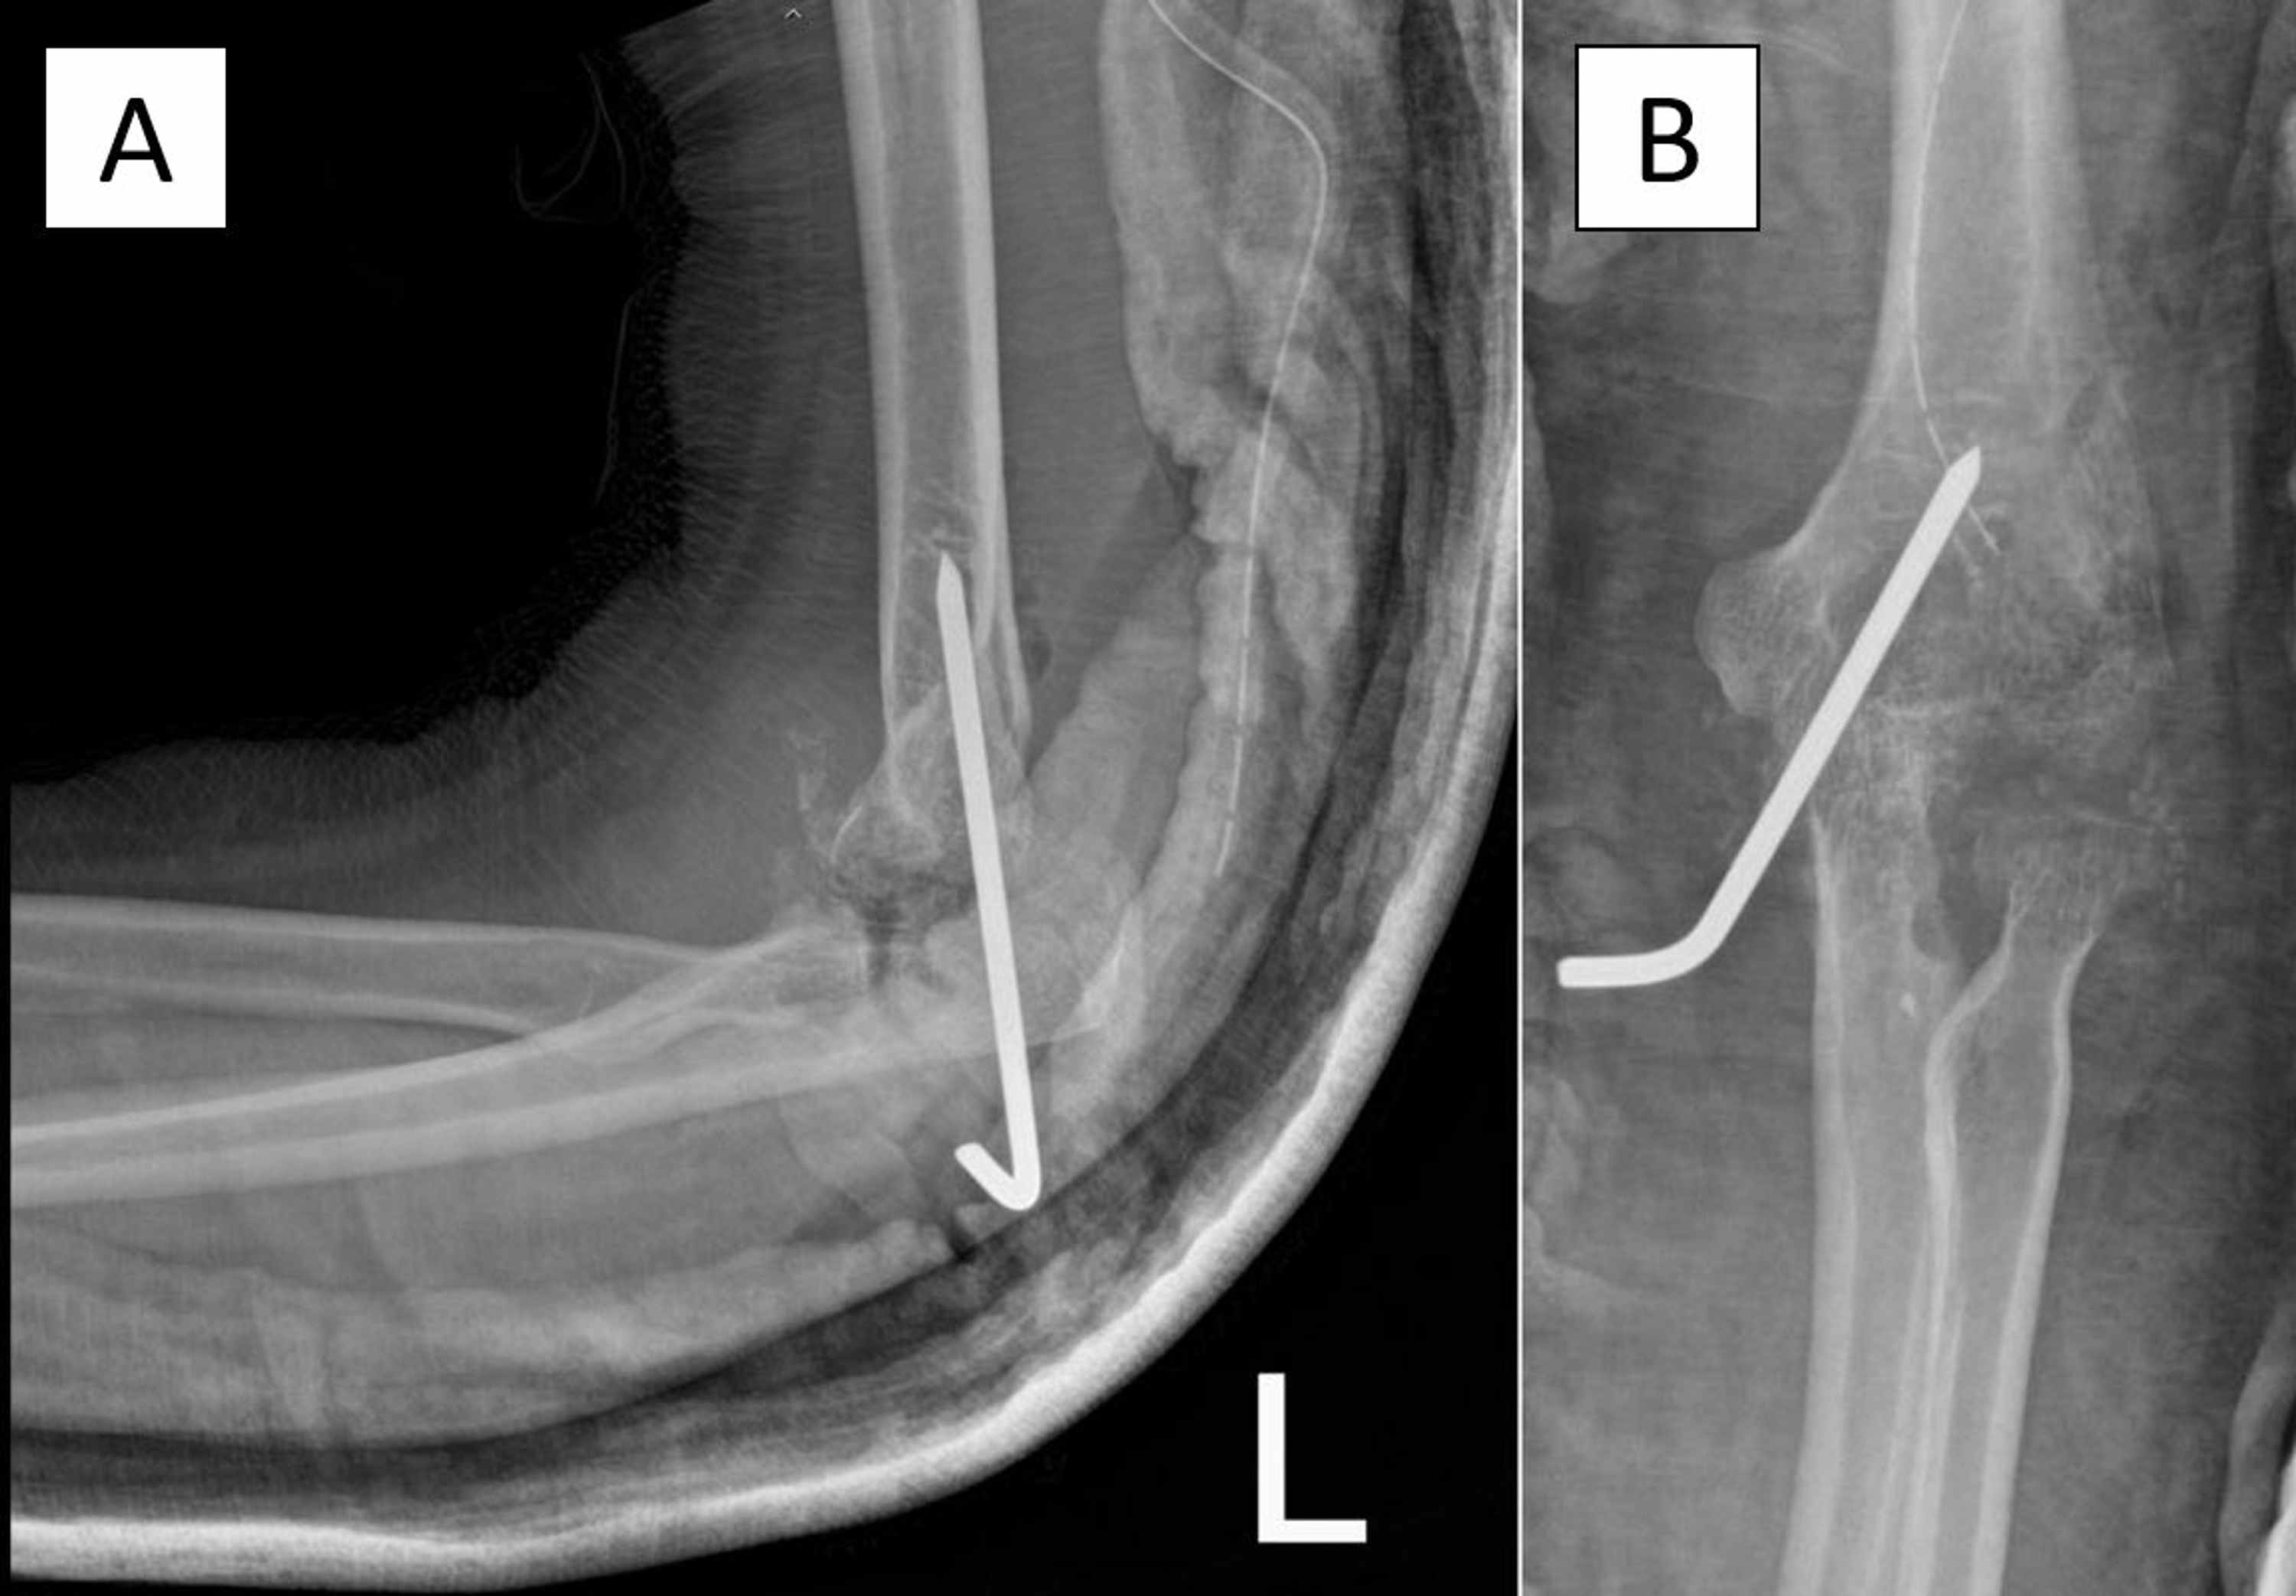

Tuberculous Arthritis Elbow Radiology . Tuberculous arthritis of the right elbow. Frontal (a) and lateral (b) plain radiographs demonstrate multiple osteolytic lesions within the ulna,. To assess magnetic resonance (mr) imaging features in differentiating tuberculous arthritis from pyogenic arthritis. Tuberculous arthropathy is a type of musculoskeletal manifestation of tuberculosis (tb) and a common cause of infectious arthritis in. Periarticular osteopenia, cortical erosion, narrowing of the joint space, minimal periosteal reaction, and calcification of. Fourteen patients with tubercular arthritis of elbow were evaluated. Mri is a highly sensitive technique which demonstrates fine anatomical details and identifies the early changes of arthritis, which are not visible on radiographs.

Tuberculous arthritis of the right elbow. Frontal (a) and lateral (b) plain radiographs demonstrate multiple osteolytic lesions within the ulna,. Periarticular osteopenia, cortical erosion, narrowing of the joint space, minimal periosteal reaction, and calcification of. Tuberculous arthropathy is a type of musculoskeletal manifestation of tuberculosis (tb) and a common cause of infectious arthritis in. Mri is a highly sensitive technique which demonstrates fine anatomical details and identifies the early changes of arthritis, which are not visible on radiographs. Fourteen patients with tubercular arthritis of elbow were evaluated. To assess magnetic resonance (mr) imaging features in differentiating tuberculous arthritis from pyogenic arthritis.

Tuberculous Arthritis Elbow Radiology Frontal (a) and lateral (b) plain radiographs demonstrate multiple osteolytic lesions within the ulna,. Tuberculous arthritis of the right elbow. Fourteen patients with tubercular arthritis of elbow were evaluated. Frontal (a) and lateral (b) plain radiographs demonstrate multiple osteolytic lesions within the ulna,. Mri is a highly sensitive technique which demonstrates fine anatomical details and identifies the early changes of arthritis, which are not visible on radiographs. Tuberculous arthropathy is a type of musculoskeletal manifestation of tuberculosis (tb) and a common cause of infectious arthritis in. To assess magnetic resonance (mr) imaging features in differentiating tuberculous arthritis from pyogenic arthritis. Periarticular osteopenia, cortical erosion, narrowing of the joint space, minimal periosteal reaction, and calcification of.

Emergency Joint Aspiration A Guide for Radiologists on Call Tuberculous Arthritis Elbow Radiology To assess magnetic resonance (mr) imaging features in differentiating tuberculous arthritis from pyogenic arthritis. Mri is a highly sensitive technique which demonstrates fine anatomical details and identifies the early changes of arthritis, which are not visible on radiographs. Tuberculous arthropathy is a type of musculoskeletal manifestation of tuberculosis (tb) and a common cause of infectious arthritis in. Frontal (a) and. Tuberculous Arthritis Elbow Radiology.